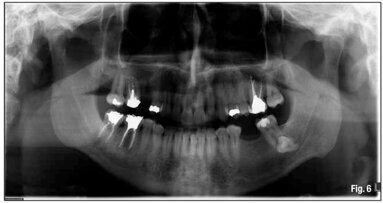

OFFENBACH, Germany: Tooth extraction is part of the day-to-day business in a dental practice. However, last year, Dr Max Lukas was fairly stunned when he ...

Misdiagnosis of an extra-oral sinus tract usually leads to a destructive invasive treatment of the local skin lesions that is not curative and often ...